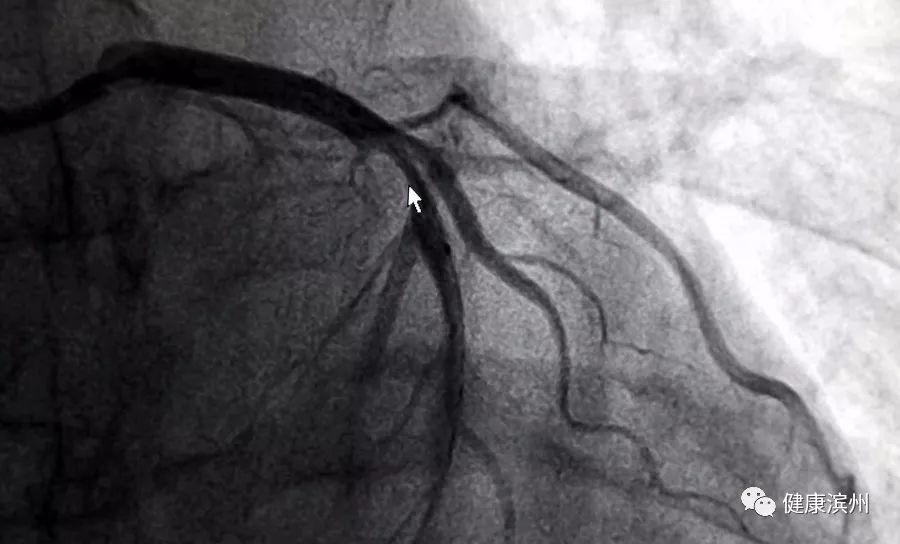

最后,讓我們一起欣賞一下“妙手回春”的美麗“春色”。術前,光標指引處,左冠狀動脈狹窄,嚴重影響了血流通暢。